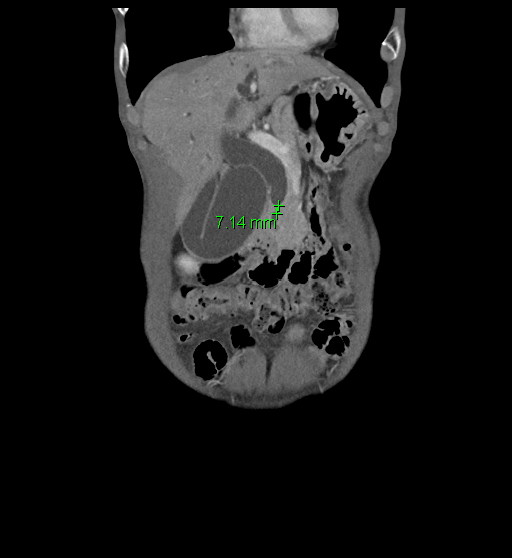

1. Multiphase CT and MRI

- High-resolution contrast-enhanced CT and MRI scans are first-line tools for evaluating biliary masses, ductal obstruction, vascular involvement, and metastatic spread.

- MRI with MRCP (Magnetic Resonance Cholangiopancreatography) is particularly useful for visualizing the biliary tree non-invasively and assessing the level and extent of bile duct strictures or masses.